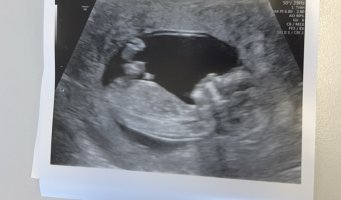

Var på TUL i dag 13+3. Hun mente det kunne se ut som jente men ville ikke bekrefte noe. Hva tror dere? :)

Jeg har ikke peiling på sånt! Men jeg synes det ser ut som en gutt, eller.. jeg vet ikke:smiley-ashamed004